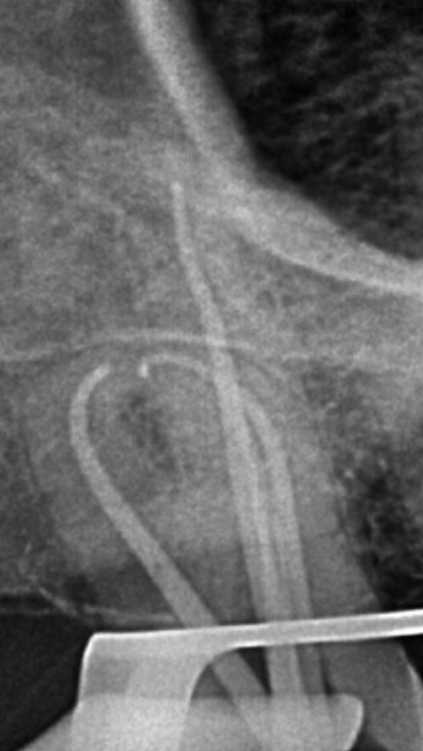

看个根充 —— 右上智齿

by Mohammad Saeid